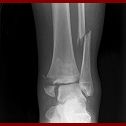

Fracture :

Pas toujours évident à repérer sur le terrain et à différencier d’une entorse, au moindre doute partez du principe que c’est cassé. Les signes qui doivent faire évoquer la fracture sont la notion de craquement, de déformation d’un membre, l’impossibilité de bouger le membre, de le mettre en appui et l’existence d’une douleur localisée.

Prise en charge :

– NB : Toute notion de craquement lors de l’accident, tout gonflement extreme ou douleur anormalement forte doit vous amener à consulter un médecin pour éliminer une fracture.